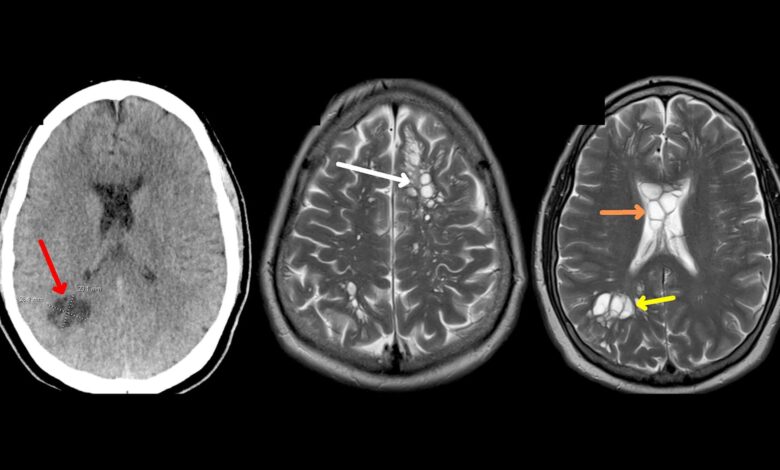

علامات خطيرة تنذر بدودة الدماغ.. احترس من لحم الخنزير

وأضافت غرونش، إلى أن دودة الدماغ هي أكثر شيوعًا دودة شريط لحم الخنزير، تينيا سوليوم (أو داء الكيسات العصبية)”.

وأفادت غرونش، إن دودة الدماغ لا يمكنها الانتقال إلى الدماغ لكن يرقاتها يمكنها ذلك، حيث تضع الدودة يرقاتها بمجرد دخولها للأمعاء مستخدمة أجسامنا كوسيط، وإذا لم يتم طرد البيض من أجسامنا من خلال البراز، فقد تنمو إلى يرقات.

وأشار غرونش، إلى أنه يمكن لهذه اليرقات أن تنتقل إلى أعضاء أخرى من خلال مجرى الدم، قد تنتقل هذه الديدان الشريطية أيضا من إنسان إلى آخر إذا كان لدى الشخص عادات غير صحية، مثل: عدم غسل يديه جيدًا بعد استراحة الحمام.

وأوضحت غرونش، أنه “قد يستغرق ظهور أعراض دودة الدماغ شهورا إلى سنوات، حيث لا تظهر الأعراض عادة إلا بعد موت اليرقات، وعندما تظهر في الدماغ”.